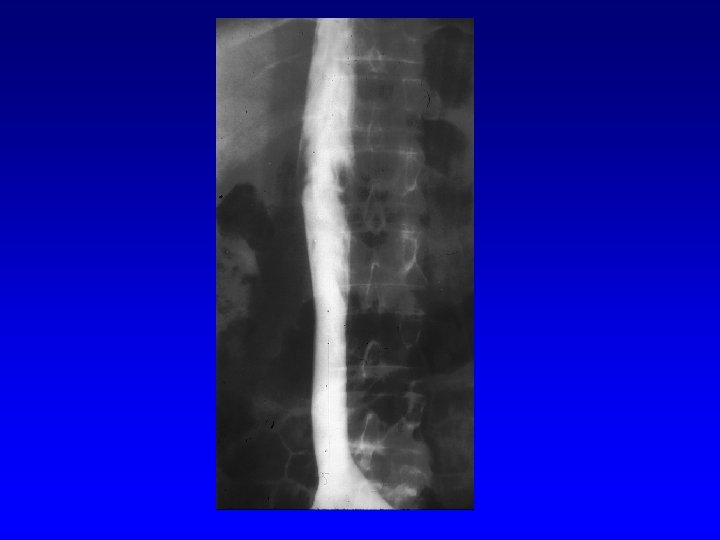

Vena Cava Filters

Current U. S. Optional Filter Designs MERIDIAN Opt. Ease™ Tulip™ Celect™ Option™ ALN ™